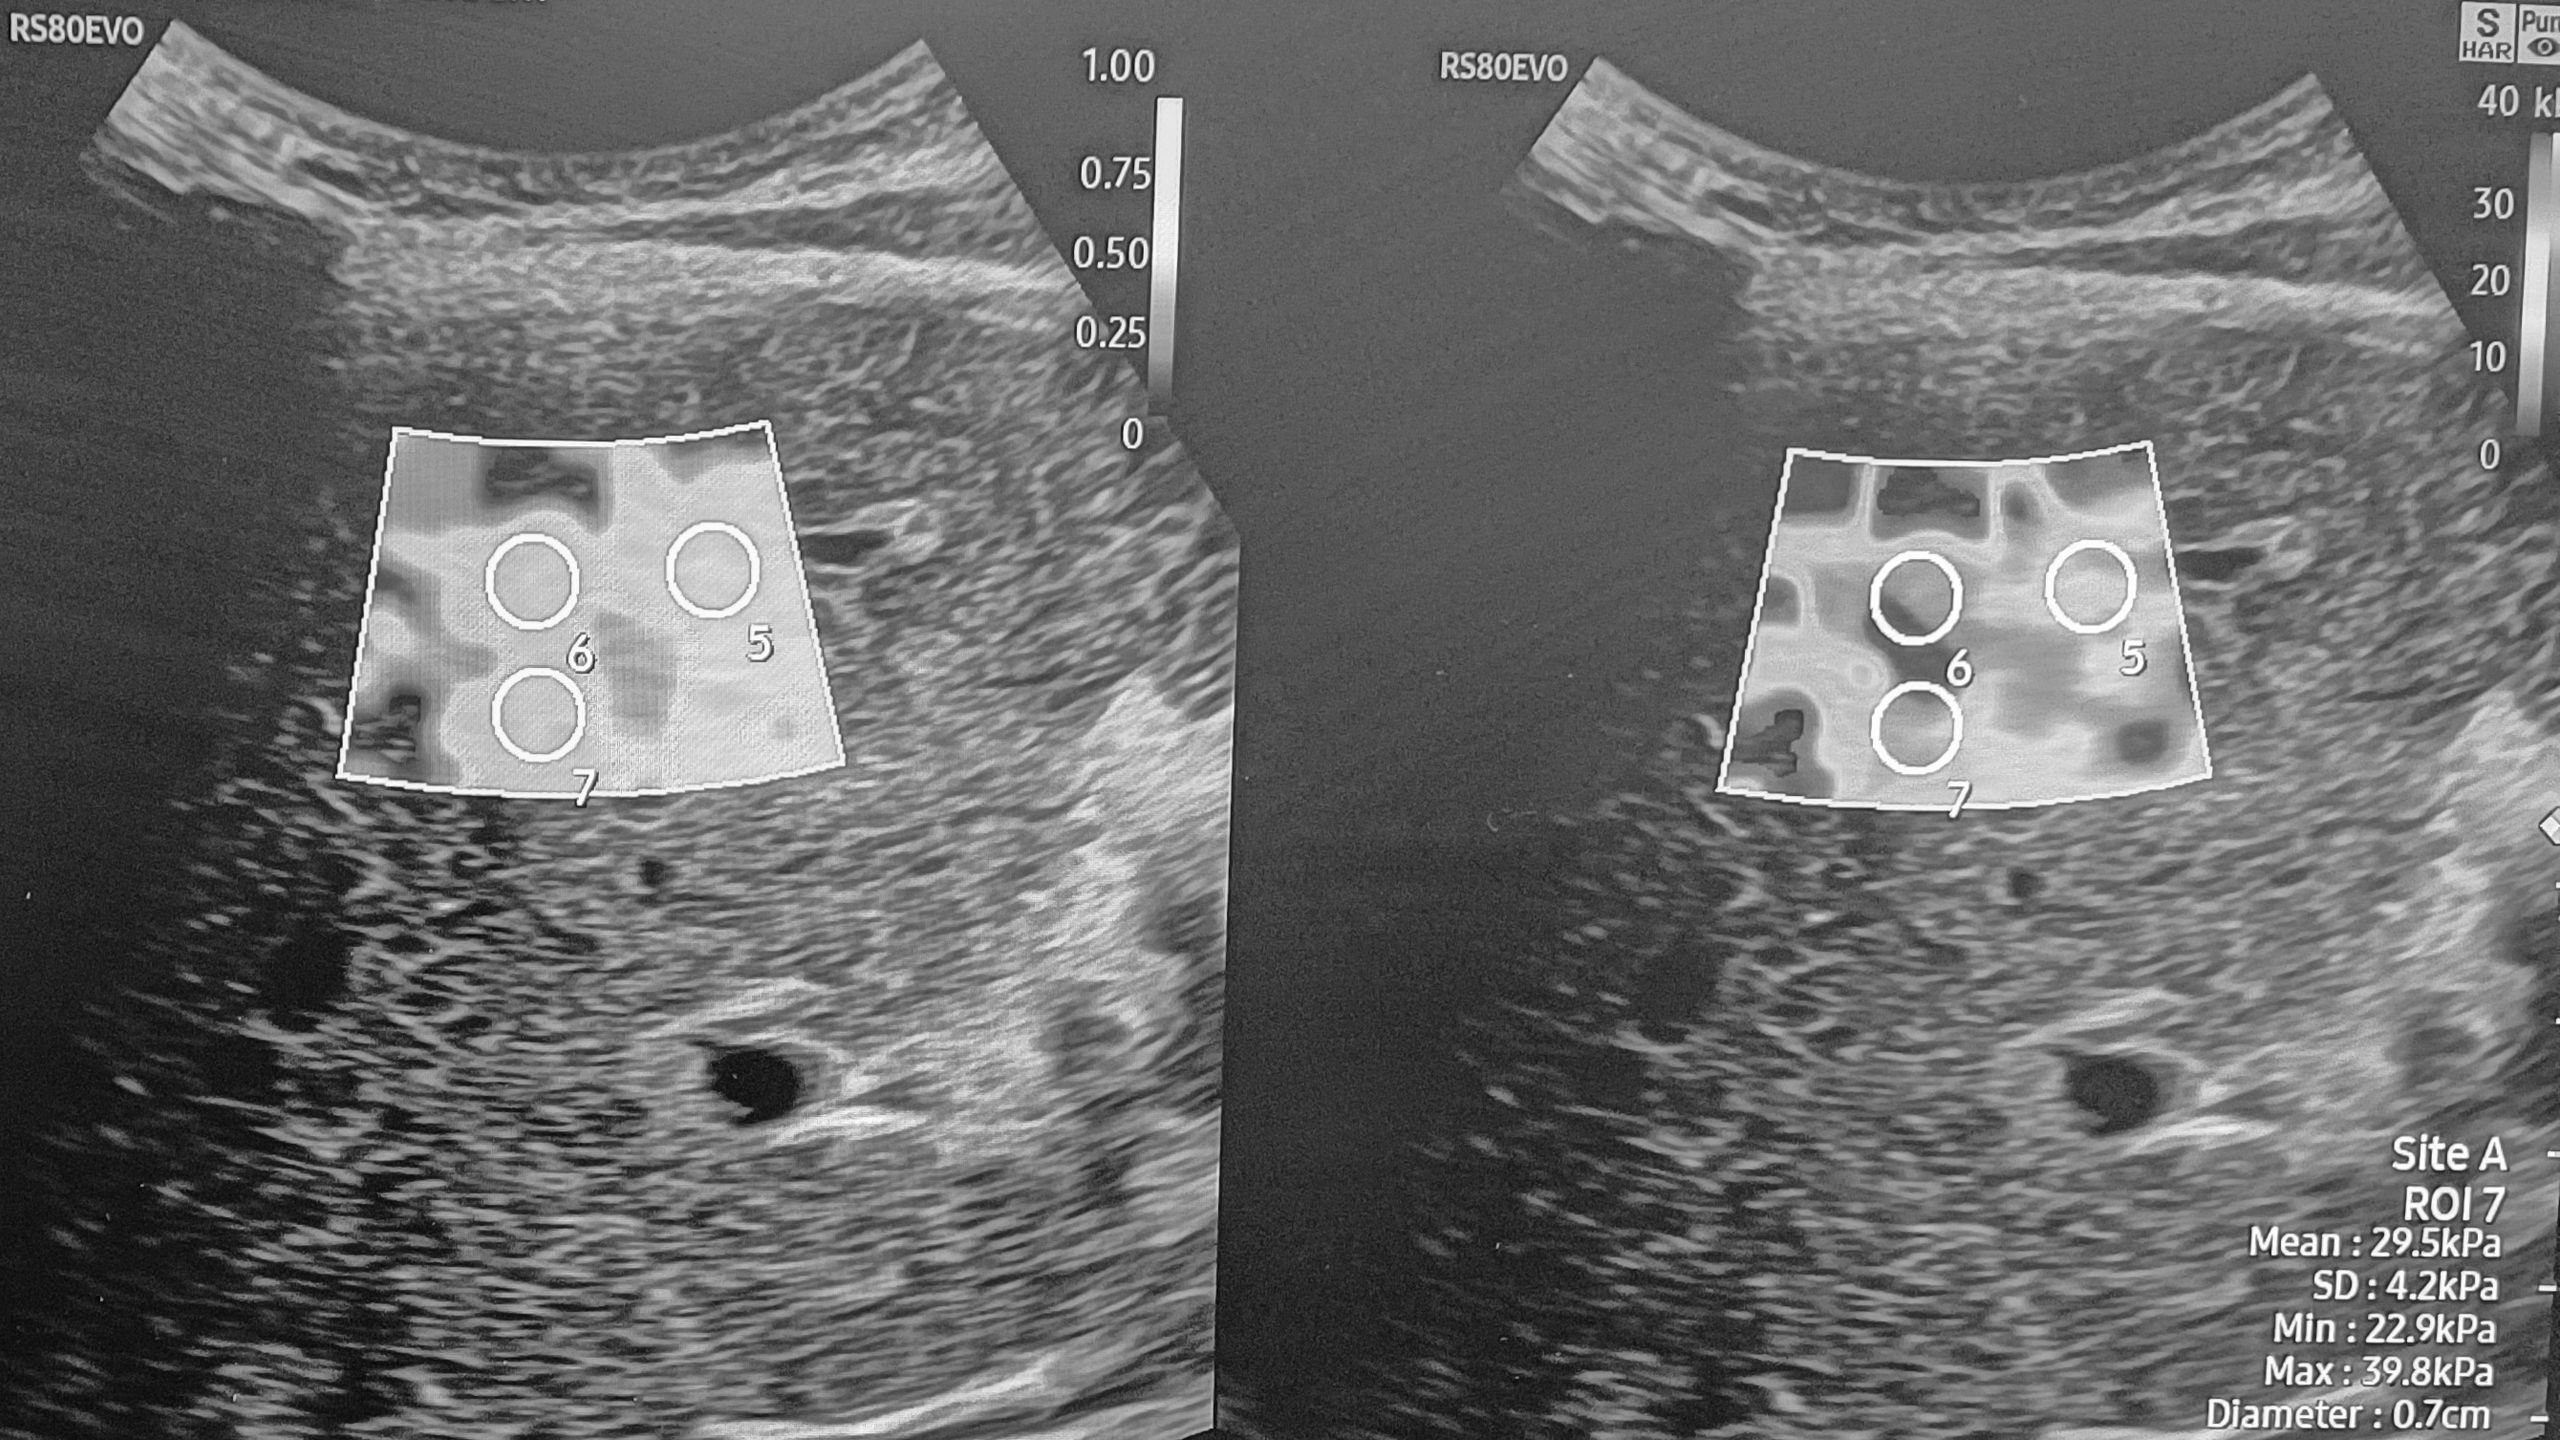

Ultrasound screening is used as it is non-invasive, cost-efficient, time-effective, widely available, portable and does not have the associated risks of cross-sectional imaging. Ultrasound can detect liver tumours as small as 1-2cm. However, it has its limitations, and the diagnostic quality can depreciate in patients with a high BMI or a liver with a fibrous echotexture. In these situations, alternative imaging can be suggested for screening and lesion characterisation.

However, contrast-enhanced ultrasound (CEUS) can provide rapid essential information. CEUS has been used for diagnostic purposes for years, and yet we are slow to uptake this in HCC surveillance.

CEUS uses intravenous microbubbles to detect and characterise indeterminate lesions. In comparison with MRI, it is quicker to perform, cheaper and has instantaneous results. Research by Auer et al 2019 proved that CEUS had the highest accuracy when diagnosing lesion <1cm over CT and MRI. CEUS can be performed during a routine surveillance scan, improving early detection and reducing patient waiting times. Furthermore, it minimises unnecessary two-week wait referrals if the lesion proves to be benign.